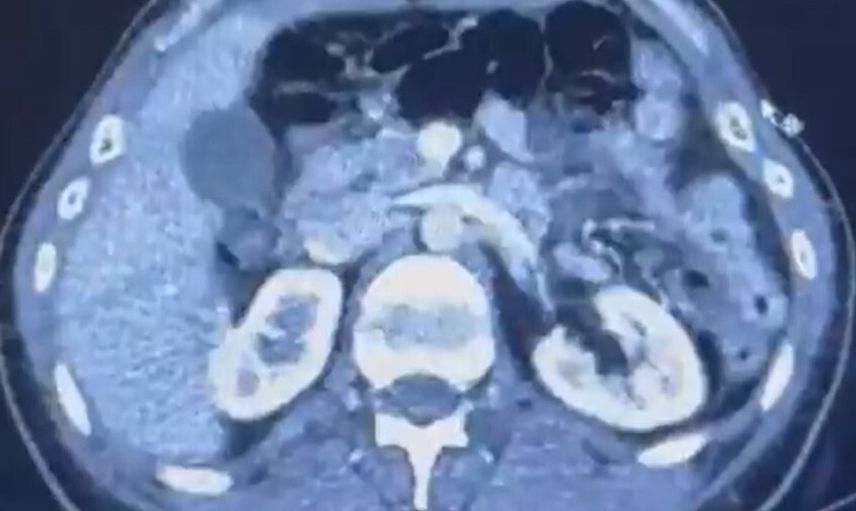

S.C. ve R.B.C.'nin Kayseri Şehir Hastanesi'nde yapılan iç beden muayenelerinde, mide bölgesinde 50 adet kapsül halinde toplam 554 gram uyuşturucu madde tespit edildi.

ŞÜPHELİLERİN MİDESİNDE KAPSÜL ŞEKLİNDE YARIM KİLO UYUŞTURUCU MADDE ELE GEÇİRİLDİ.